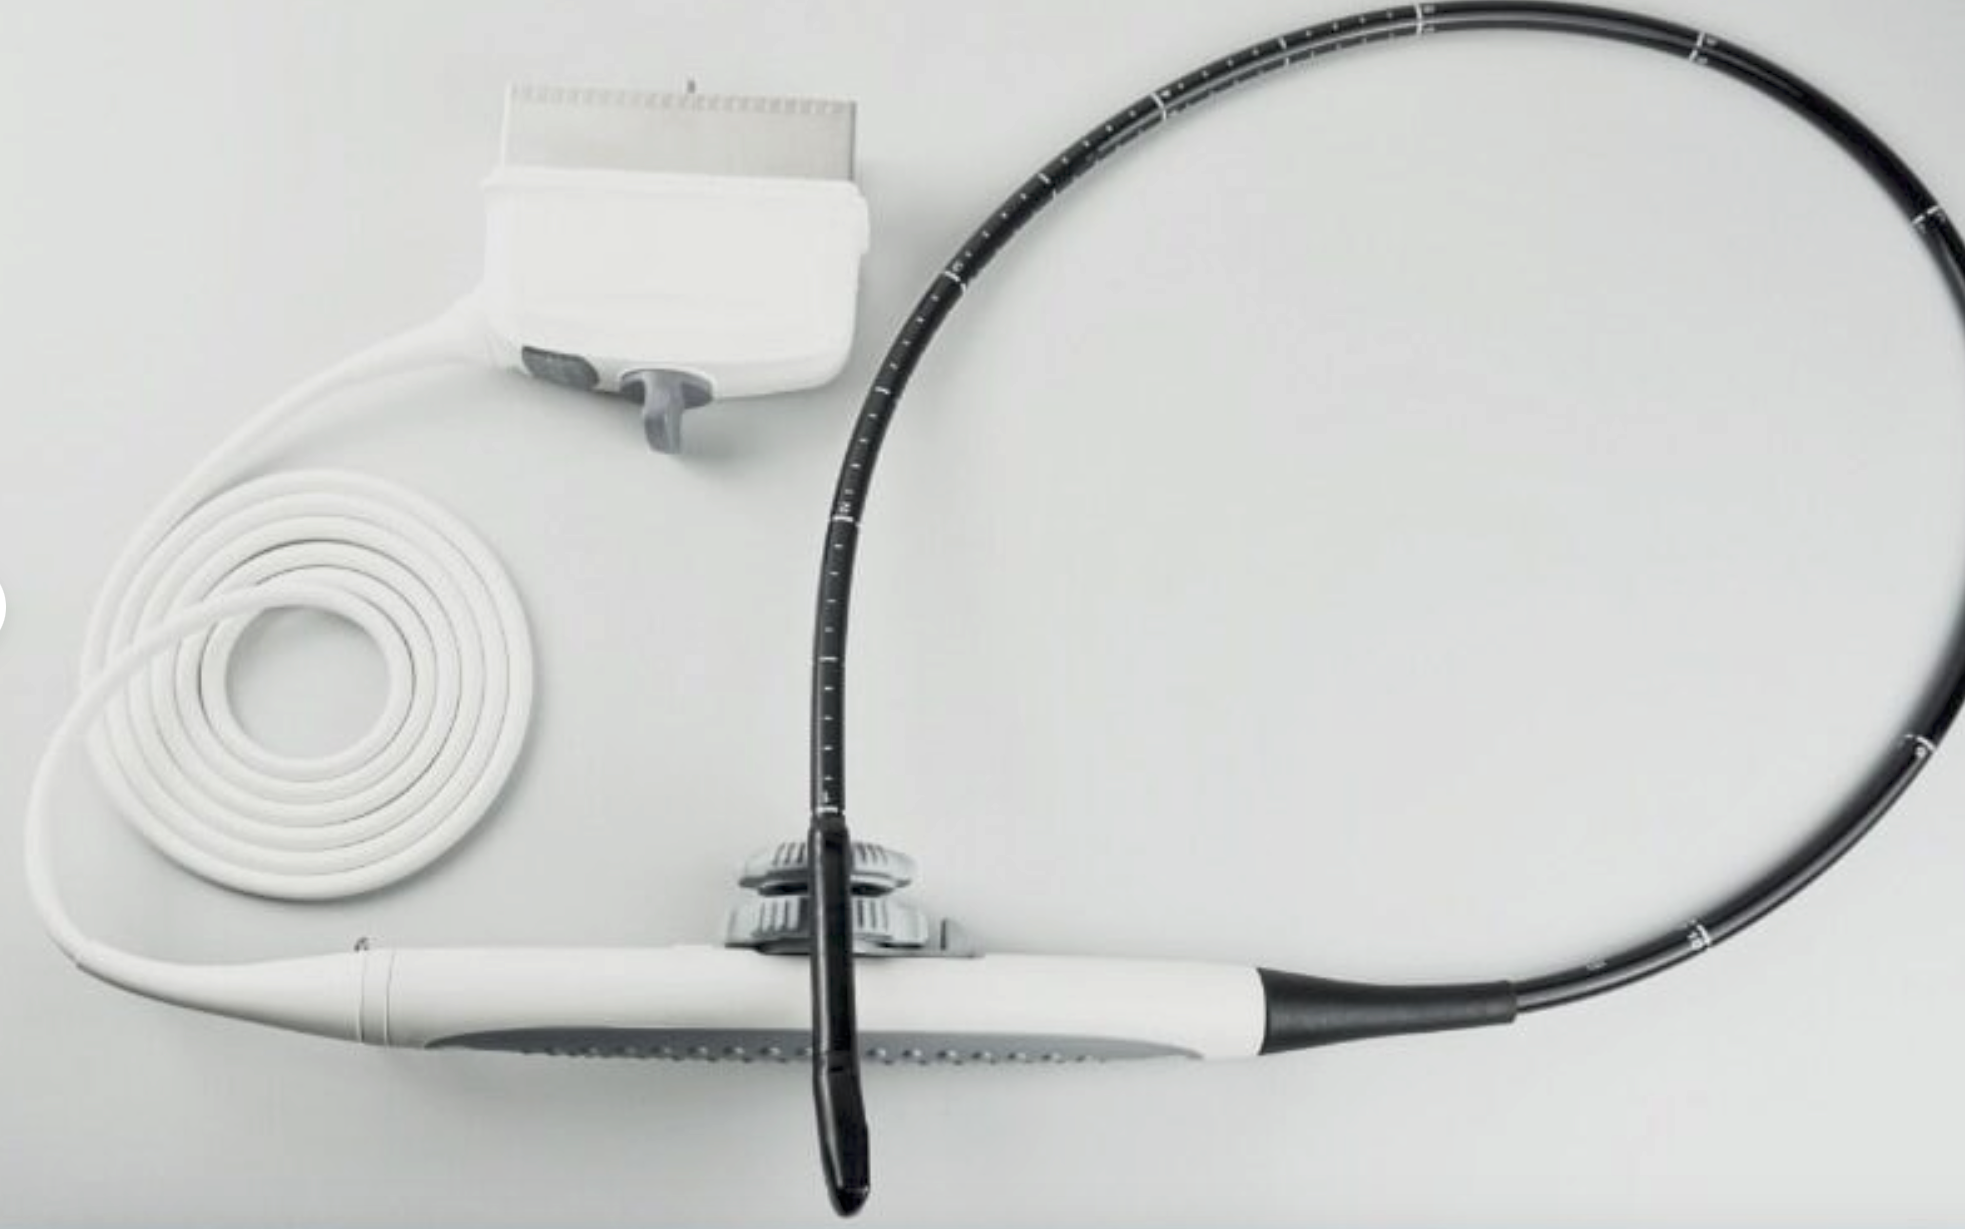

Veterinary Touch Screen-Reptiles, Equine Ultrasound&Linear Array Probe, KeeboMed